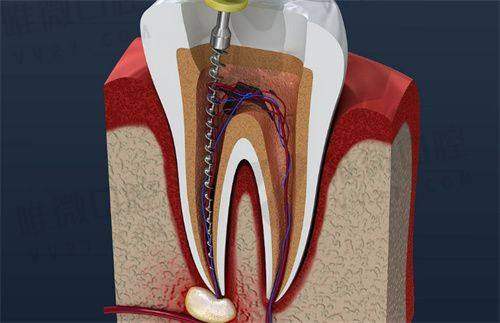

根管治疗,是拯救牙齿避免拔除的关键手段,尤其是当蛀牙伤及牙髓或导致牙根感染时,选择合适的医院进行科学治疗就尤为重要。面对琳琅满目的口腔机构,特别多小伙伴都在问:广州根管治疗去哪家医院好?各家医院的收费标准是多少?本文将通过整理2025年的真实数据和用户反馈,为您呈现广州根管治疗性价比高、口碑佳的六家口腔机构,助你明明白白看牙!

优势解析:穗华口腔是一家拥有广东省卫生健康委员会认证的正规机构,设有完整的八大专科科室,尤其在根管治疗方面先引入Schilder-Yu 3D显微根管技术,倡导“三维充填,保护牙神经”的理念。医院环境舒适,整体就诊体验非常温馨,非常适合对治疗过程舒适度关注较高的患者。